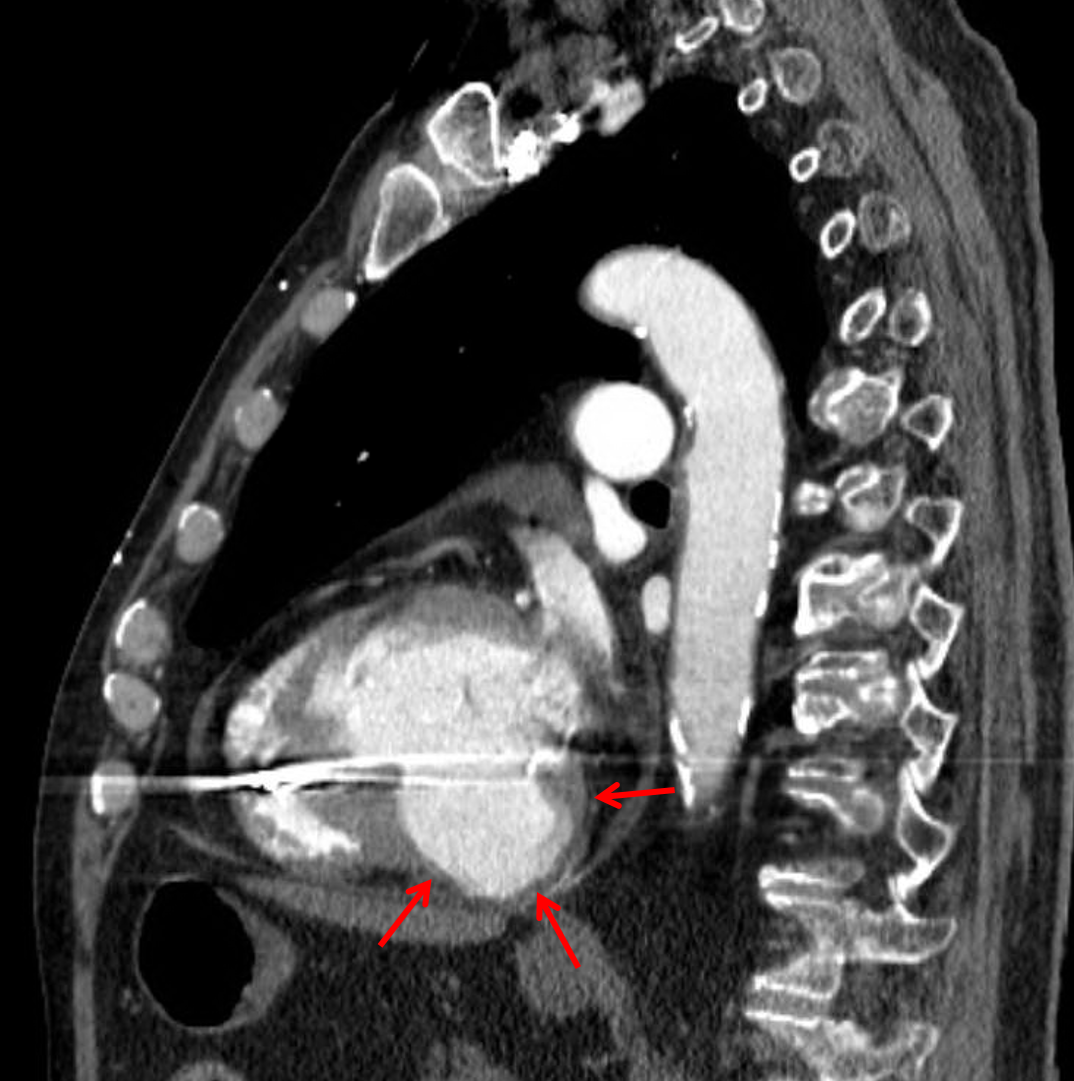

Outpouching arising from the inferior wall of the left ventricle most suggestive of a false aneurysm (pseudoaneurysm).